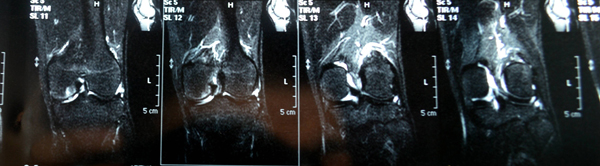

【附图1 使用软骨粉前 2015年5月初】

【附图 使用软骨粉后 2015年7月底】